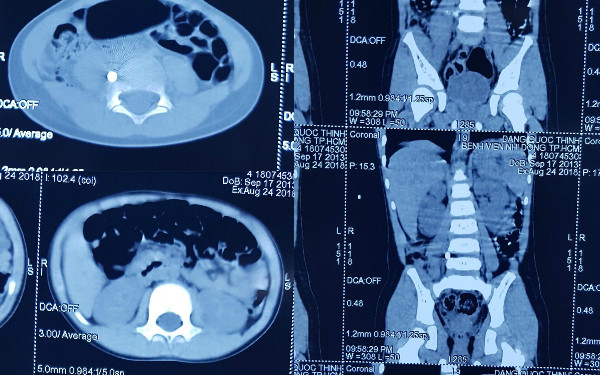

| Viên đạnxuyên thấu vùng thắt lưng bé trai. |

Bác sĩ Tạ Huy Cần, trưởng kíp mổ cho biết viên đạn xuyên thấu vùng thắt lưng, nằm trong đĩa đệm đốt sống, ngay trước rễ thần kinh tọa và thần kinh đùi. Nếu viên đạn đi chếch ra sau một chút có thể làm đứt hệ thống rễ thần kinh này, nguy cơ cao liệt người. Nếu đạn chếch trước một chút sẽ đi xuyên qua bó mạch chủ nơi chia mạch chậu, bé nguy hiểm tính mạng.